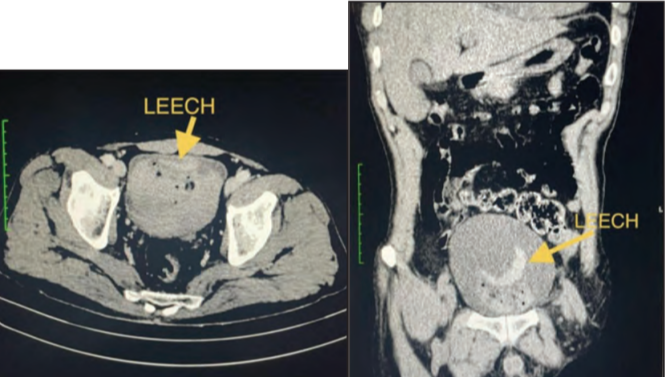

Figure 2. Компьютерная томография. На аксиальных и коронарных снимках брюшной полости с контрастированием видны трубчатые структуры в мочевом пузыре со сгустками крови, что наводит на мысль о пиявках